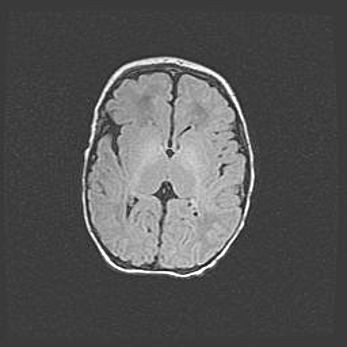

Открытая гидроцефалия.

Возраст: 9 месяцев 12 дней

Вес: 6800 г

Пол: мужской

Окружность головы: 41,5 см

Срок гестации: 28 недель

Гидроцефалия головного мозга у новорожденных имеет характерный признак: опережающий рост окружности головы приводит к визуально хорошо определяемой гидроцефальной форме сильно увеличенного в объёме черепа. Детские неврологи определяют следующие симптомы гидроцефалии у грудничков: выбухающий напряжённый родничок, частое запрокидывание головы, смещение глазных яблок к низу.